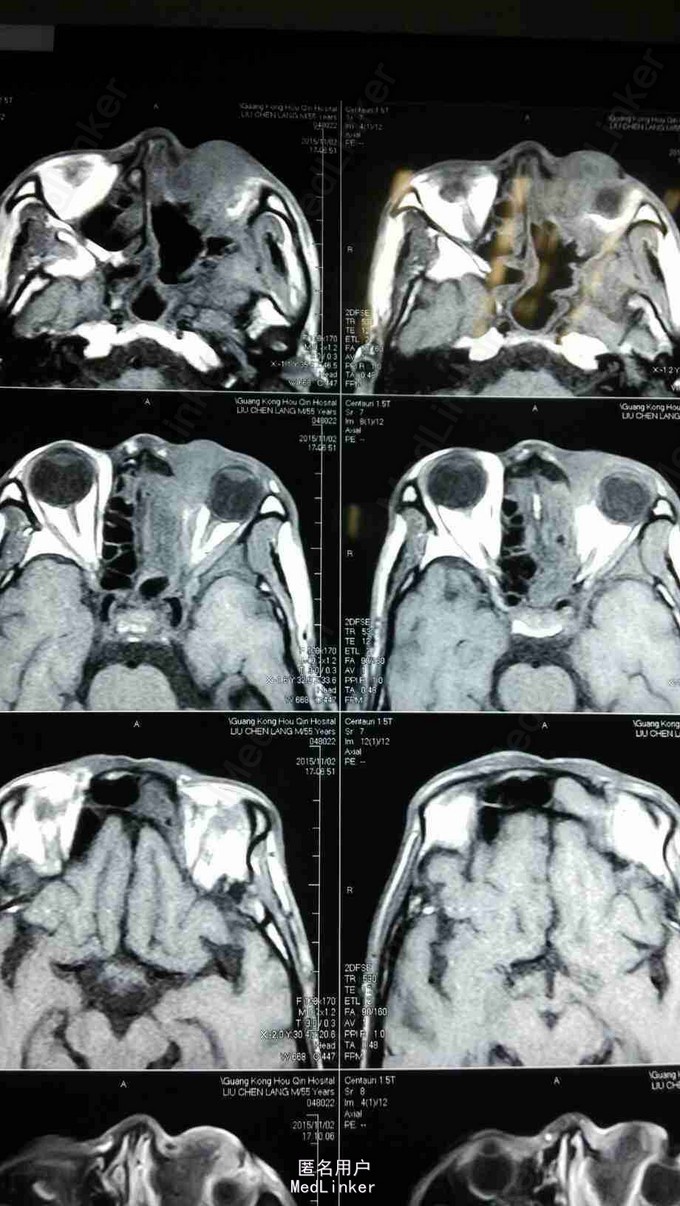

查体:患者神清,消瘦,发音不清,全身浅表淋巴结未见肿大,左眼上睑内侧可见肿物,大小约1*1cm,皮肤红肿,无破溃,质硬,伴压痛,不活动,眼睑闭合不全,睫毛方向正常,眼部可见少量脓性分泌物。 MRI:左侧上颌窦术后改变,左上颌窦顶壁及左眼眶内下方异常信号,考虑肿瘤复发,累及左眶内眦部,前组部分筛窦,内下方肌间隙及上下眼睑内侧份。